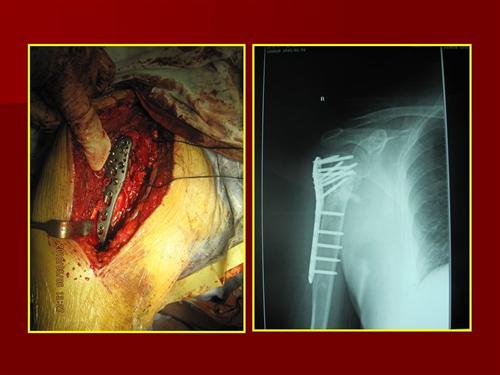

相关图片